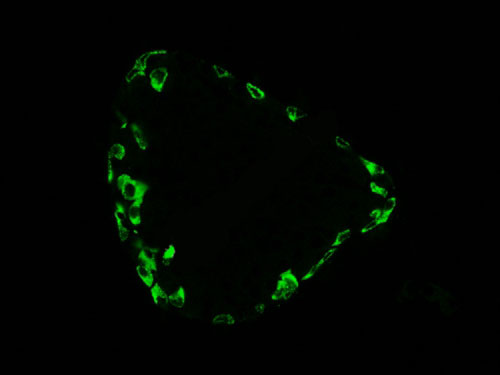

熒光顯微鏡是免疫熒光的基本工具。它是由光源、濾板系統和光學系統等主要部件組成。是利用一定波長的光激發標本發射熒光,通過物鏡和目鏡系統放大以觀察標本的熒光圖像。

正置顯微鏡型號:NIKON Eclipse ci;軟件:NIS_F_Ver43000_64bit_E;成像系統:NIKON digital sight DS-FI2。可選擇100×、200×和400×不同放大倍數。共配置紅、綠、藍三個通道:DAPI(EX激發340-380,BA發射435-485);FITC(EX激發465-495,BA發射515-555);G-2A(EX激發510-560,BA發射590)

實驗結果展示:

(3)實驗結果:圖片×6,每張圖片包括merge圖,單通道圖(常規選擇同視野下200×3、400×3)